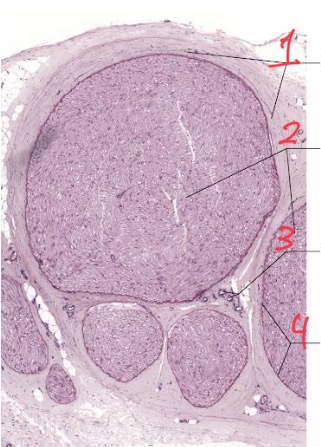

1

Interfasicular epineurium

2

Nerve fascicles

3

Vasa nervorum

4

Perineurium

What is this

Peripheral nerve cross section